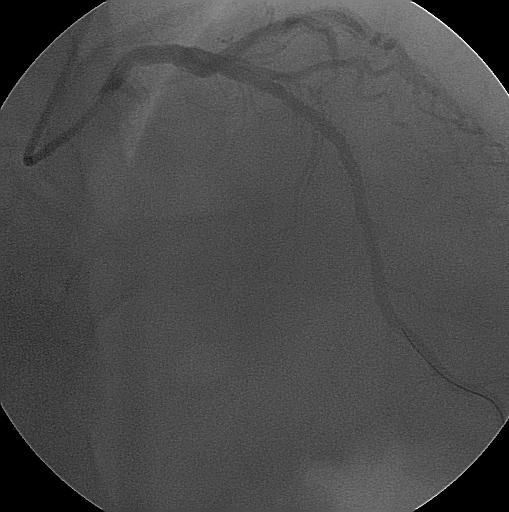

Koroner balon uygulamasında, daralmış veya tıkanmış olan koroner damar bölgesine ince bir tel üzerinden balon ilerletilerek darlık veya tıkanıklık üzerinde şişirilir ve ve darlık açılır, balon işleminden sonra genelde damarda biraz darlık kalır ve ileride aynı bölgenin tekrar daralma riski yaklaşık %40-50'dir. Şeker hastalarında, ince damar çapı olanlarda, darlık bölgesi uzun olanlarda bu oran daha da yüksek olabilir.

Koroner stent uygulamasında ise darlık veya tıkanıklık bölgesine bir balonun üzerinde sıkıştırılmış tel kafes bulunur, bu üzerinde tel kafes olan balon darlık bölgesinde şişirilince üzerindeki tel kafes genşileyerek damar duvarına gömülür ve darlığı dışarı doğru iter, sonra balon indirilip geri çekilir, stent o bölgede kalır, yaklaşık 4-6 hafta sonra stentin üzeri damar katmanı ile örtülür, yani damar KORONER STENT

içinden bakılınca stent gözle görülmez. Stent uygulama işleminden sonra aynı bölgede tekrar daralma olması riski yaklaşık %30-40'dır, ama yine şeker hastalarında, ince damar çapı olanlarda, darlık bölgesi uzun olanlarda bu oran daha da yüksek olabilir.